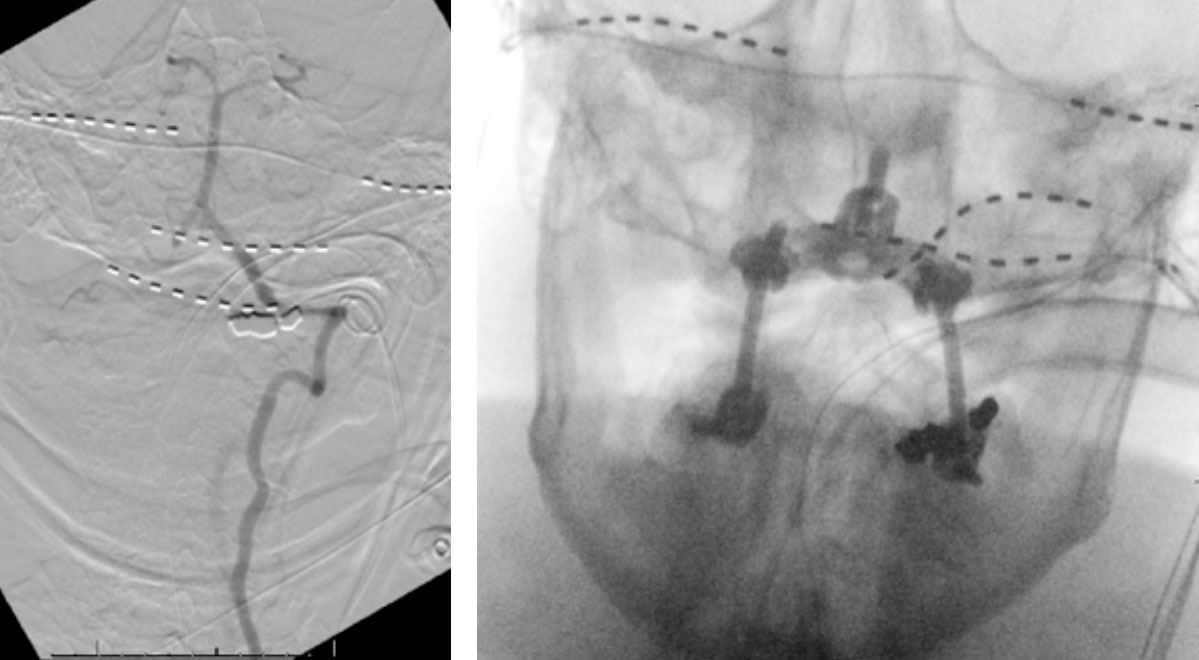

CTA of the neck and brain reveal that the left Vertebral Artery is completely occluded at approximately the C1-C2 level with extensive hypertrophic degenerative osseous changes from C1-C3. Retrograde flow into the post PICA left Vertebral Artery is observed from the co-dominant right Vertebral Artery which appears to be the primary supply into the basilar circulation. No significant Posterior Communicating arteries are observed on either the right or left Carotid Artery on the CTA imaging (Figure 1).

We performed conventional catheter angiography with provocative testing to reproduce his symptoms. The right Vertebral Artery is the codominant primary supply to the basilar circulation with reflux into the distal left Vertebral Artery that is occluded (Figure 3).